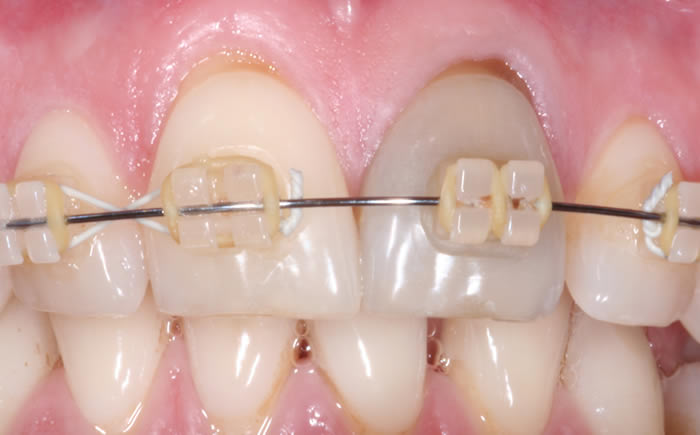

More front teeth replaced by dental implants

Case Three (4 images)